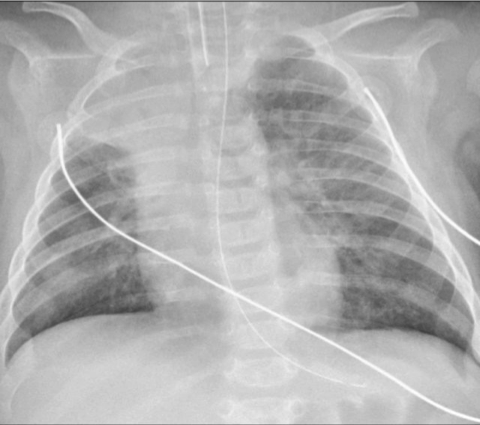

X-ray finding

• Hyperinflated lungs.

• In 30% scattered areas of opacity due to consolidation or atelectasis.

• An X-ray of a child with RSV showing the typical bilateral perihilar fullness of bronchiolitis.

Chest radiograph of a 3-month-old infant with severe RSV bronchiolitis: demonstrating a collapsed right upper lobe, hyperinflated left lung and bilateral perihilar, peribronchial thickening. The patient is intubated and has a nasogastric tube in situ.